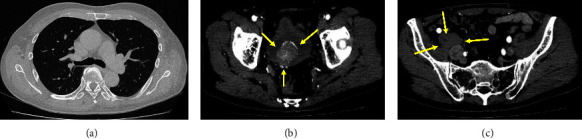

Small cell neuroendocrine carcinoma is rare among urinary bladder cancer types, and to date, there are no case reports of concurrent antitranscriptional intermediary factor 1-γantibody-positive dermatomyositis. We describe the case of a 69-year-old Japanese man who presented with elevated creatine kinase levels and haematuria on medical examination. Approximately one month later, he developed dysphagia. Laryngoscopy confirmed laryngeal dysfunction. He also presented with muscle weakness and a skin rash. Magnetic resonance imaging of the upper extremities suggested bilateral brachial muscle myositis. He was diagnosed as having dermatomyositis and was later found to be positive for antitranscriptional intermediary factor 1-γ antibody. Computed tomography revealed an intravesical space-occupying lesion and right iliac lymphadenopathy, suggesting urinary bladder cancer. The patient was admitted to our hospital for treatment. Urinary bladder biopsy confirmed small cell neuroendocrine carcinoma because tumour cells were positive for synaptophysin, CD56, and chromogranin A. Thus, the patient was diagnosed as having an antitranscriptional intermediary factor 1-γantibody-positive dermatomyositis concomitant with urinary bladder small cell neuroendocrine carcinoma. The patient was treated with glucocorticoid and intravenous immune globulin therapy for dermatomyositis. Radiotherapy was selected for the carcinoma. Although muscle weakness and skin symptoms improved with treatment, dysphagia persisted. Furthermore, expression of the transcriptional intermediary factor 1-γ protein in tumour cells was also confirmed by immunohistochemistry, but the significance is unknown. It should be noted that antitranscriptional intermediary factor 1-γantibody-positive dermatomyositis can occur concomitantly with such a rare malignancy.